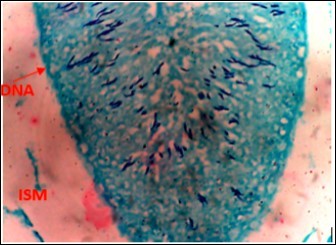

Figure 3.Normal Control (NC) X400 – Section of testis showing numerous deeply stained DNA with magenta color.

From findings in this study, irregular and distorted arrangements of DNA in all diabetic groups (Groups B, C, D, E and F) when compared with the normal control group, may have been due to displacement of sertoli cell within the germinal epithelium of seminiferous tubules. Strands of DNA were also seen arrange in clusters in diabetic groups, showing altered and defective structure which might have resulted from base free side deletion, frame shift, cross-linking and chromosomal rearrangement. The intensity of magenta colour development in Feulgen reaction for DNA demonstration was proportional to DNA concentration. There was reduced colour intensity in all diabetic groups (Groups B, C, D, E and F) when compared with the normal control. This is in line with report from Aitken and Krausz (2001). However the degree of distortion and cross-linking of DNA strand in the group of diabetic animal models placed on high dose (1000mg/kg.bw) of A. polytricha which may be a sign of amelioration. Groups C, D and F placed on 250mg/kg.bw A. polytricha, 500mg/kg.bw A. polytricha and standard anti-diabetic drug (metformin) respectively did not show remarkable differences in terms of DNA arrangements when compared with the diabetic control group. Groups D (500mg/kg.bw A. polytricha) and group E (1000mg/kg.bw) showed visible improvement in magenta colour intensity when compared with the diabetic control group.